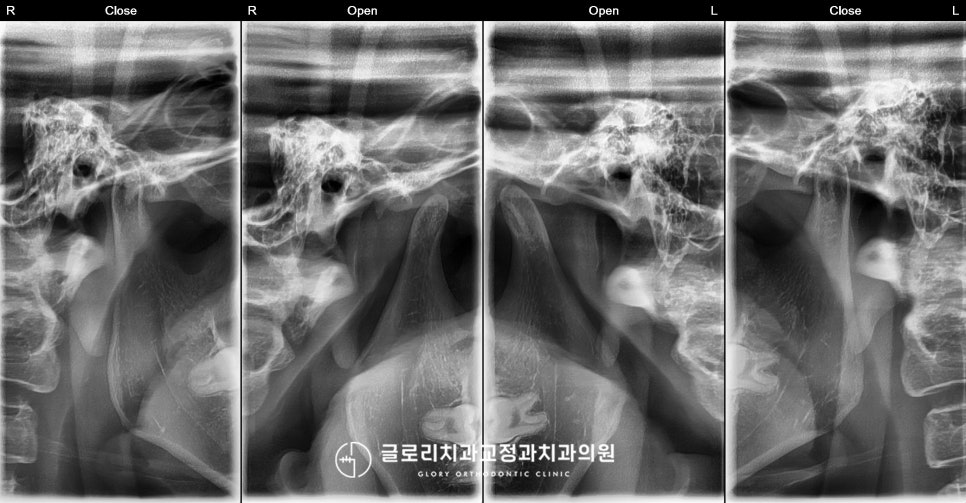

『2. 시작 전 턱관절(TMJ) 체크』

치료를 시작하기 전

턱관절에는 문제가 없는지도

꼼꼼하게 살펴보았습니다.

간혹 앞니 치아교정을 시작한 뒤

턱관절의 통증을 호소하시는 경우가 있어

망우역 치과 의 엑스레이와 CT를 촬영해

꼼꼼하게 확인한 뒤 진행을 하는데요.

이 환자의 경우

진료 전 TMJ와 과두에는 문제가 없으나,

중간에 재위치되어 움직일 경우

치료 계획이 변경 가능성이 존재합니다.

그렇기 때문에 월마다 오셔서

치열과 더불어 TMJ에도 불편한 점은 없는지

면밀히 체크해 드리기로 했습니다.